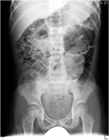

1. 小児急性腹痛で最も多い原因は便秘症である。

1. 便秘症の90%以上は原因が特定できない機能性便秘症である。

1. 治療開始時、fecal impaction(便塞栓)が存在する場合、まずはdisimpaction(便塊除去)を行うことが推奨される(推奨度2)。